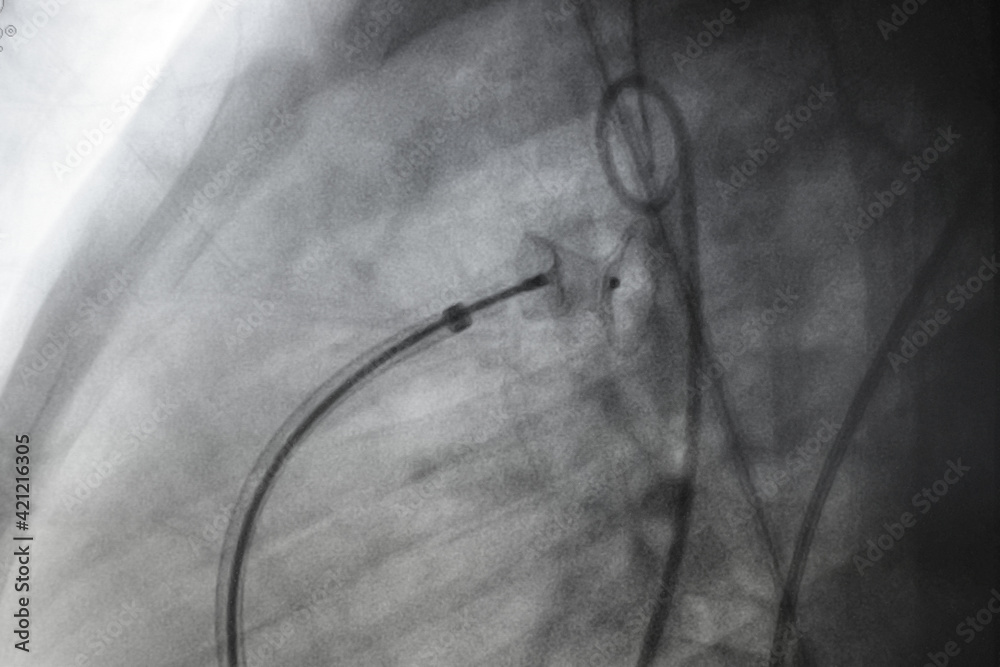

x ray image perform PDA device closure after treatment patent ductus Pda Device In Heart a long, thin flexible tube (catheter) is inserted in a blood vessel, usually in the groin or wrist, and guided to. The persistent opening causes too much blood to flow to. patent ductus arteriosus (pda) is a congenital condition in babies that causes heart and lung problems. a device is then threaded through the catheter and placed. Pda Device In Heart.